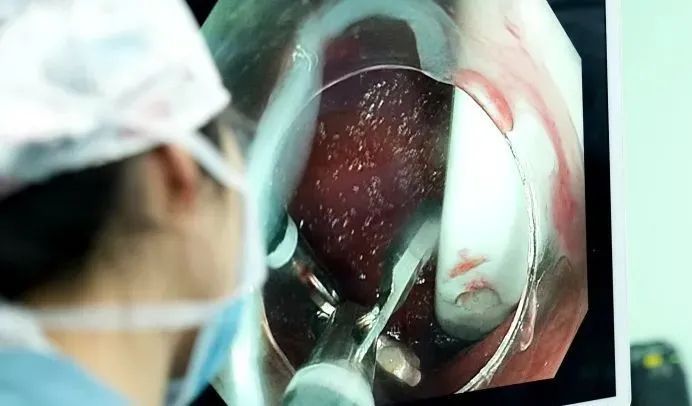

时间分秒流逝,周平红教授果断启用创新方案——双钳协同术。

首先,经内镜通道送入异物钳A,夹持另一把异物钳B抵达勺柄处;

随后,钳B夹住勺柄小孔向下推送,使勺体与镜身平行;双钳配合把整个勺子从狭窄危险的十二指肠区域,慢慢拖回到相对宽敞的胃里。

最后,周教授换回更牢固的“套圈”工具,稳稳套住勺柄,最终顺着食道,成功将这把15厘米长的陶瓷勺子完整地取了出来!